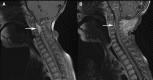

A 22-month-old girl presented with neck pain and stiffness and magnetic resonance imaging showed an extradural mass extending from C2 through the C4 level with moderate to severe compression of the cord. A left unilateral C2-C4 laminectomy was performed revealing an extradural rubbery tumor; a small biopsy was obtained. Examination of stained tissue revealed the presence of a parasitic worm that was identified as a gravid female Onchocerca lupi. A magnetic resonance imaging at 7 weeks follow-up showed a significantly decreased size of the enhancing lesion and the patient's symptoms gradually resolved. This is the first report of zoonotic O. lupi in the United States. The parasite has been reported in dogs and cats in the western United States, and from people in four cases reported from Europe. A great deal more needs to be learned, including full host range and geographic distribution, before we fully understand O. lupi infections in animals and man.